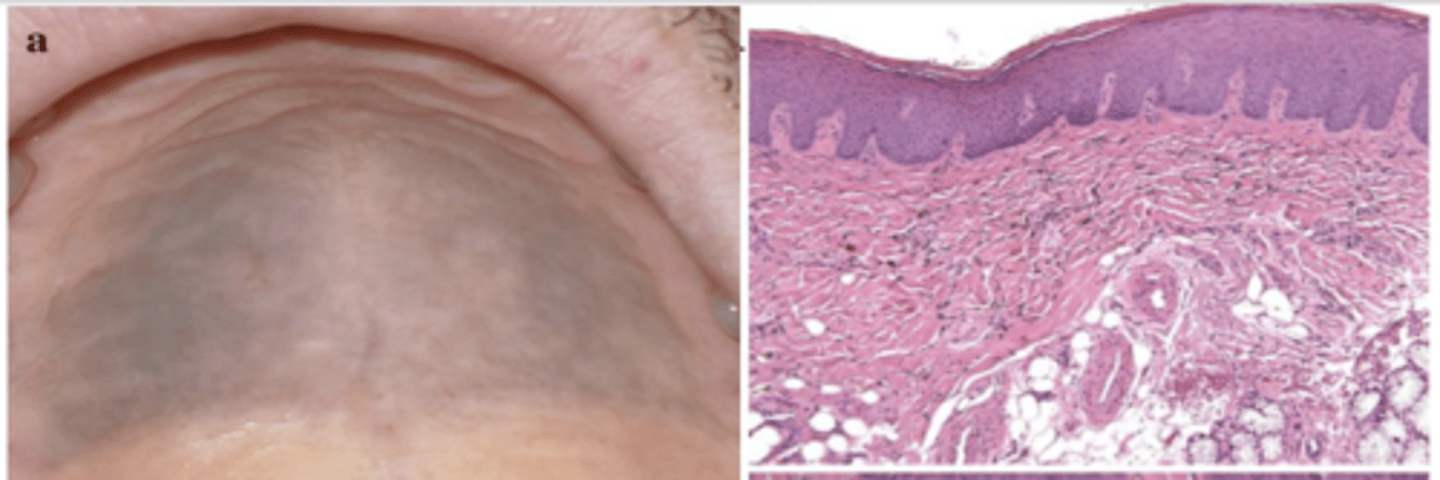

What type of pigmented lesion?

medication-induced pigmentation (typically palatal mucosa)